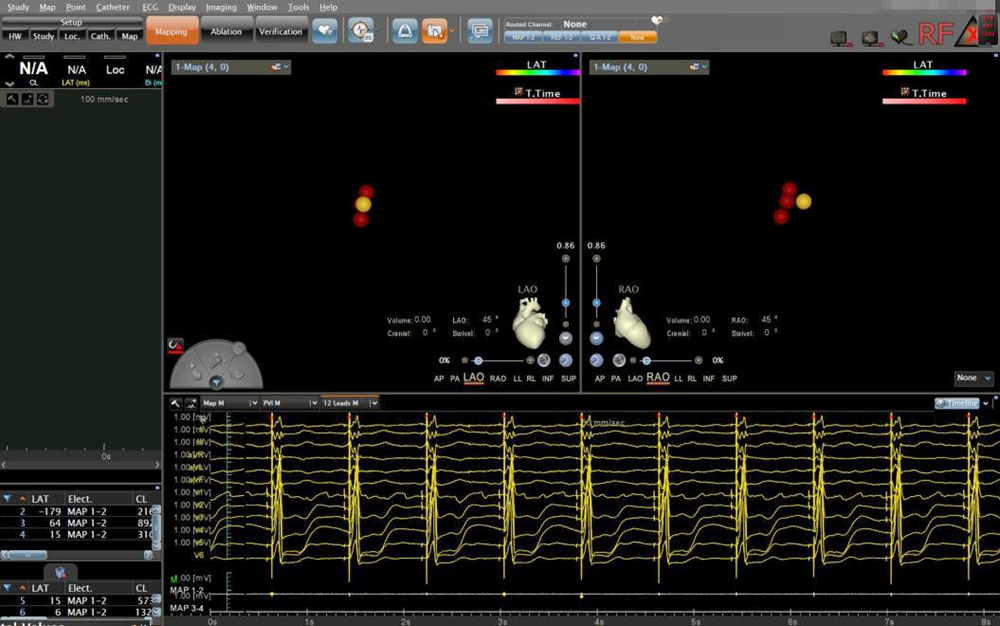

▲房室结消融靶点图及腔内心电图